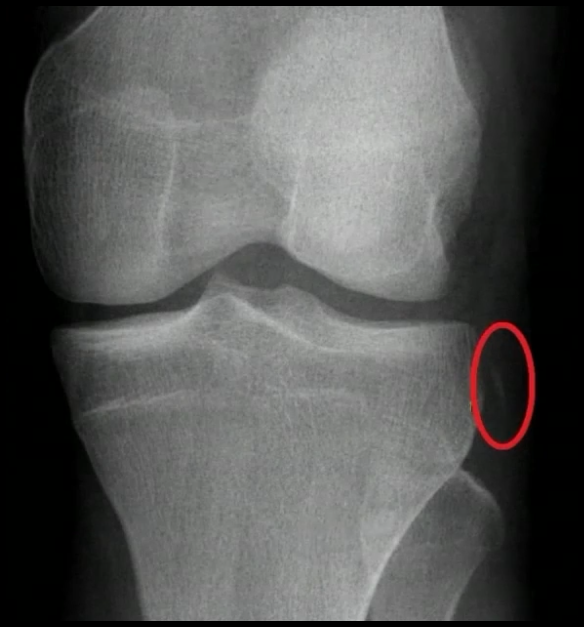

Exame de Imagem: RX ?

A

Investigar Lesões Associadas

Lesão de Segond → Patognomônico de lesão LCA